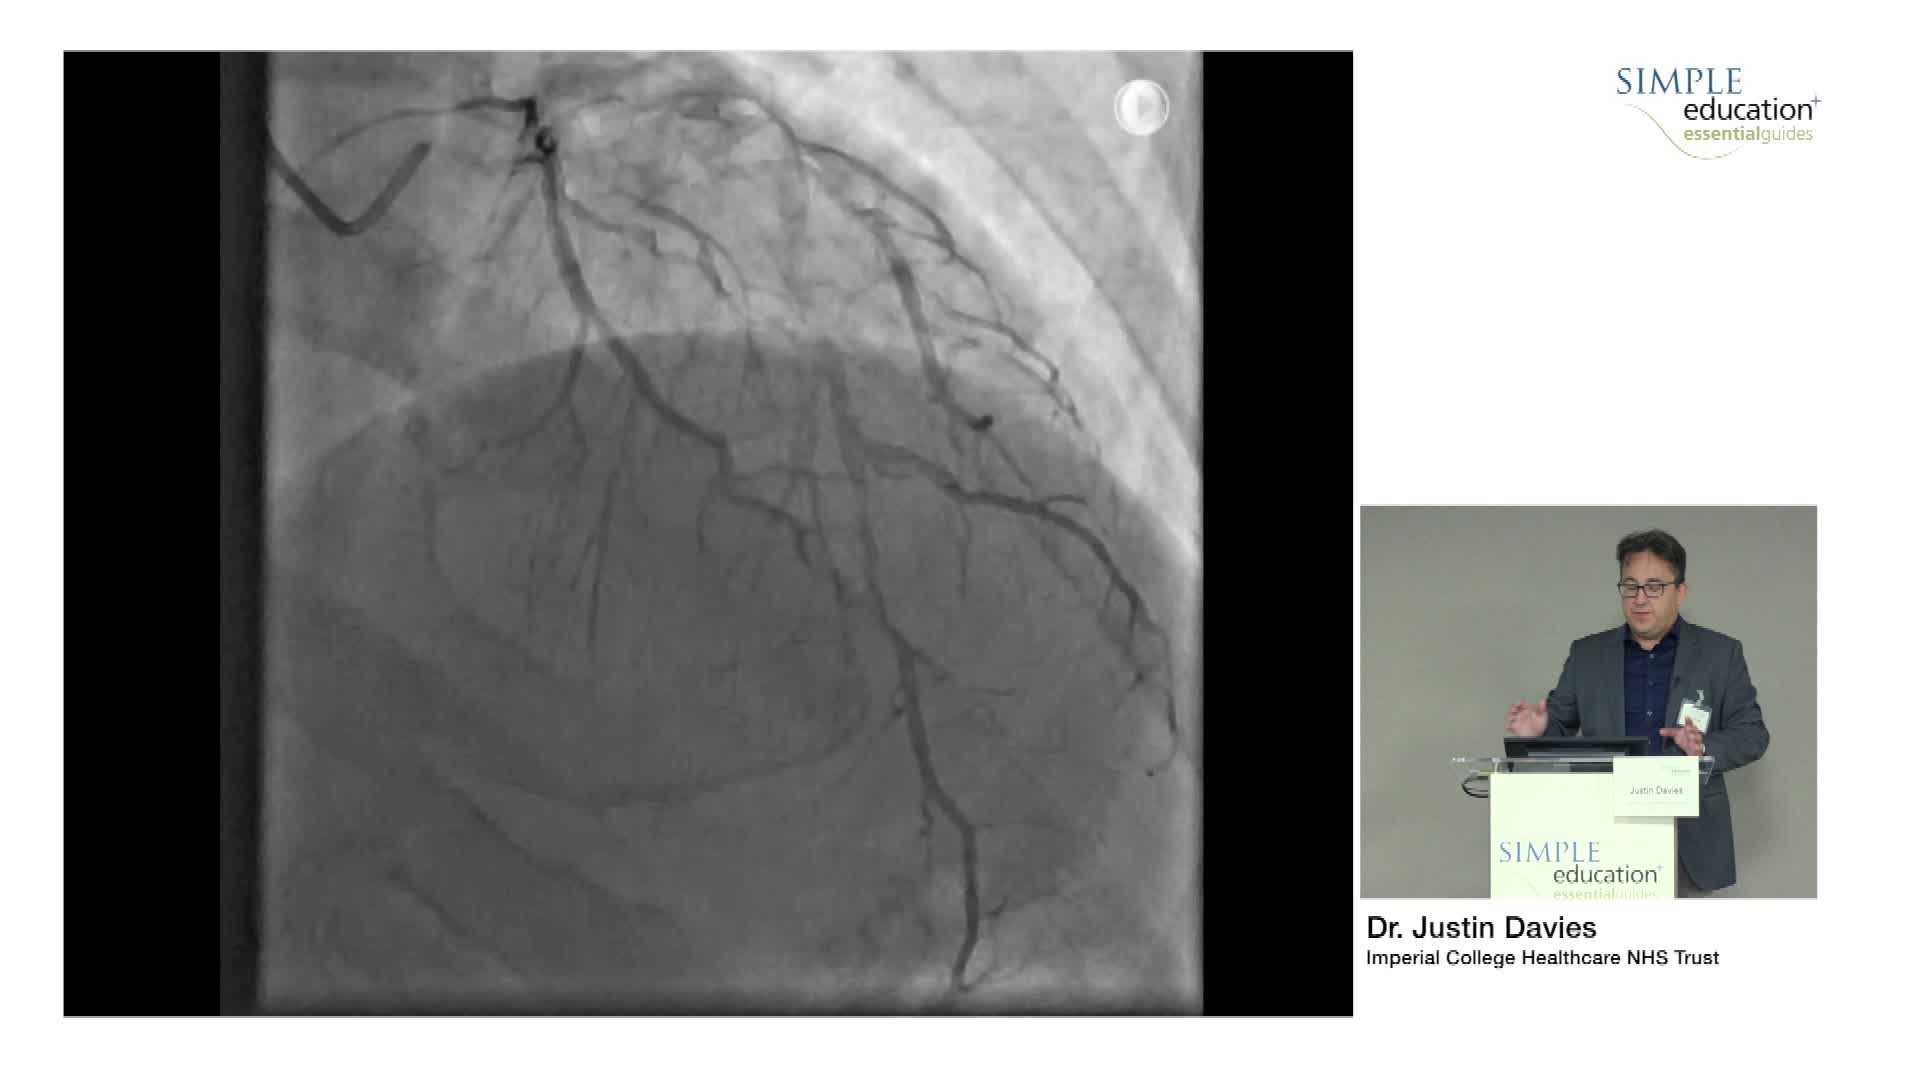

- Instantaneous wave-Free Ratio (iFR)

- Fractional Flow Reserve (FFR)

- Coronary Flow Reserve (CFR)

- FFR-CT

20 year overview of clinical trial data to support the use of coronary physiology in revascularisation decision-making - Prof Carlo Di Mario